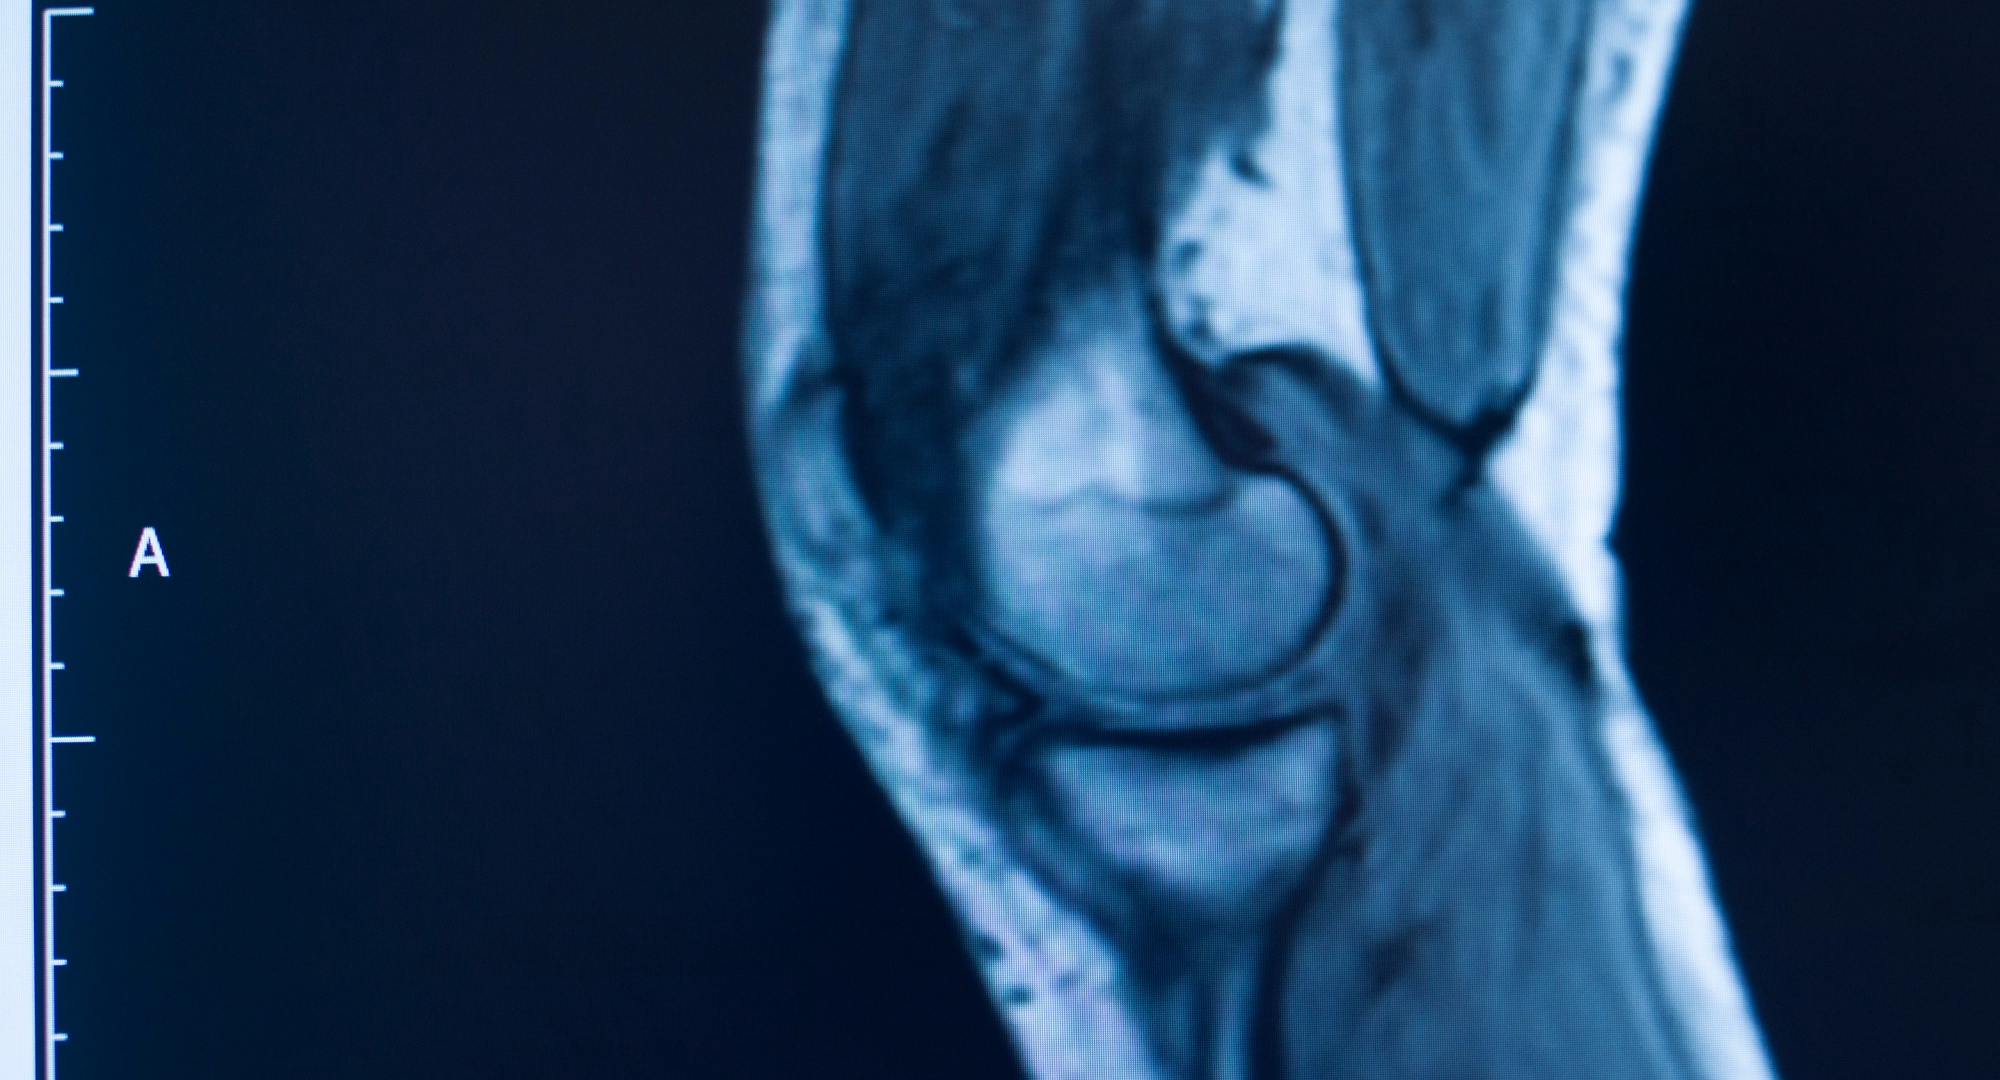

Koljeno je najčešće ozlijeđeni dio tijela kod skijaša. Ozljede ligamenata, posebno prednjeg križnog ligamenta (ACL) i medijalnog kolateralnog ligamenta (MCL), predstavljaju značajan dio teških ozljeda u skijanju. Rupture ACL-a često prate ozljede meniskusa i mogu zahtijevati kirurško liječenje i dugotrajnu rehabilitaciju. Studije pokazuju da su ozljede koljena najčešće u alpskom skijanju.

Za neke ozljede (npr. moguća ruptura ACL-a) trebali biste izbjegavati nepotrebno naprezanje i što prije potražiti ortopeda/traumatologa radi pregleda i dijagnoze (klinički pregled + rendgenska snimka ili magnetska rezonancija).

Ako sumnjate na rupturu ACL-a (iznenadna bol, "pucanje" u koljenu, brzo oticanje, nestabilnost), potrebna je hitna ortopedska procjena i obično magnetska rezonancija (MR) kako bi se potvrdilo i planiralo liječenje (konzervativno ili kirurško). Dugoročni ishod ovisi o težini ozljede, dobi i razini aktivnosti pacijenta.